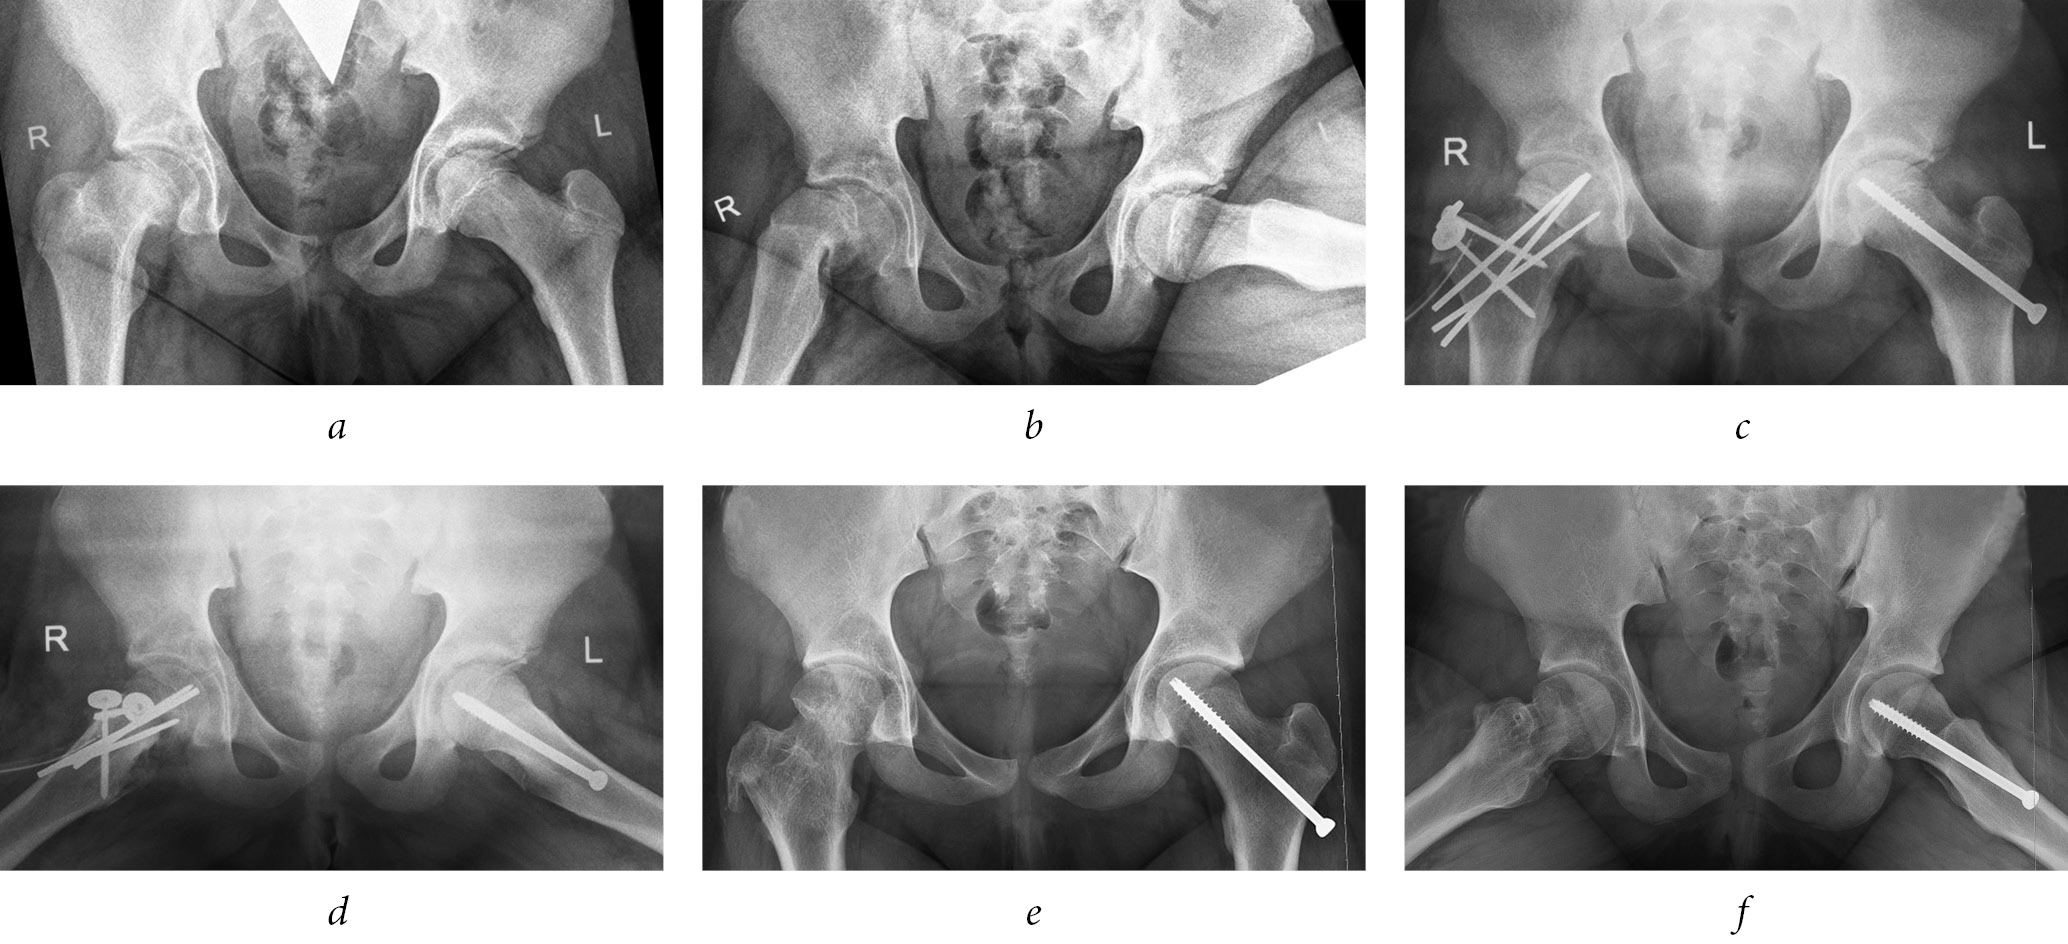

Fig. 4. Radiographs of the hip joints in the anteroposterior projection and in the Lauenstein projection of patient Z., 12 years 1 month. Diagnosis of slipped capital femoral epiphysis of the stage III on the left and stage I on the right: a, b — before the surgery; c, d — immediately after the surgery; d, e — 1.5 years after the surgery

An X-ray examination of the first two patients 1.5 years after the surgery in the reconstructed joints showed no signs of aseptic necrosis of the femoral head or chondrolysis. There was no subluxation of the femoral head, and the latter had a spherical shape, due to which congruency of the articular surfaces was preserved. The shape of the femoral component of the joint as a whole was approaching normal, with the exception of some shortening of the femoral neck and the associated moderately high position of the greater trochanter. However, the apex of the latter, being above the center of the femoral head, still did not reach its upper pole. Under the influence of axial load on the limb, regional osteoporosis decreased significantly (Fig. 4). A slight gait disturbance occurred only with prolonged walking. Despite the moderate hypotrophy of the muscles of the buttocks and hips remaining on the side of the lesion, the Duchenne-Trendelenburg symptom was negative. The relative limb shortening in one case was 1.0 cm, and in the other case, it was 1.5 cm. The Drehmann symptom and the impingement test were negative, while a slight (15°) limitation of the amplitude of the internal rotation of the hip was still determined in both joints. The patients received rehabilitation treatment (exercise therapy, massage, and physiotherapy) under conditions of a sparing load regime and compensation of limb shortening with individual insoles.

One year after surgery, a clinical and radiological examination was performed on the first five patients. Radiographic signs of aseptic necrosis of the femoral head were found only in one of them, in the joint, in which epiphysis necrosis had already begun, according to the previous study. The entire epiphysis was involved in the focus of necrosis, a pronounced deformity of the latter was seen, which deteriorated the congruence of the articular surfaces. In the remaining four cases, the femoral head was spherical in shape and had practically no structural abnormalities; however, some shortening of the neck was still noted. Regional diffuse osteoporosis was moderately expressed in both the pelvic and femoral joint components. The X-ray joint gap in these joints along the entire length remained at a normal height, which indicated the absence of chondrolysis. No disorders of joint stability were noted in any of the cases. Clinical manifestations on the lesion side in these four patients were represented by moderate muscle hypotrophy of the buttock and hip, relative shortening of the limb from 0.5 to 1.5 cm and limitation of the amplitude of the internal rotation of the hip. A child with aseptic necrosis of the femoral head complained of pain during movements of the affected joint. The flexion-adduction contracture of the hip began to form, due to which a functional shortening of the limb appeared. Further treatment of this patient with the aim of suppressing inflammatory phenomena in the joint and increasing the amplitude of hip movements was performed using cuff traction. A gradual increase in the supporting load on the affected leg was recommended to all four pediatric patients with positive dynamics, with complete rejection of crutches within a month and partial compensation for shortening.

Upon X-ray examination of the first seven patients, 6 months after the surgery, in all cases, the spatial position of the epiphysis and the greater trochanter had not changed, and there were signs of completion of consolidation at the osteotomy level. In two cases, the initial phenomena of aseptic necrosis of the femoral head were noted, but in five others, there was a significant decrease in the severity of the epiphysis osteoporosis. There were no signs of hip chondrolysis in any cases. Clinically, in five joints with positive X-ray changes, an even greater increase in the amplitude of hip movements was revealed, and in one of the joints with incipient epiphysis necrosis, there was a slight decrease associated with the development of secondary synovitis. In all seven patients, at month 7 of the postoperative period, the hardware was removed.

On radiographs a month after the surgery, in all 10 cases, stable fixation of the epiphysis and greater trochanter was noted without loss of correction of their position and initial signs of consolidation at the level of osteotomies. In six of the eight joints with diffuse osteoporosis of the epiphysis, its severity increased slightly, and osteoporosis of the epiphysis appeared in two more joints. In a clinical study, none of the patients had a vicious position of the limb, but its relative shortening persisted; in four cases, the latter increased by 0.5–1.0 cm. In all patients, the amplitude of the hip movements increased significantly, with soreness at the extreme points. The Drehmann symptom in all joints was negative.

Radiography of the hip joints in standard projections was also performed on the operating table immediately after completion of the intervention. These radiographs mainly evaluated the spatial position of the epiphysis after correction and the correct location of the hardware installed. The minimum residual displacement (within 5°) was maintained in 6 out of 10 affected joints (posterior to downward in 2 cases, only posterior in 3 cases, and only downward in 1 case). Hypercorrection of the epiphysis position was not allowed in any case.